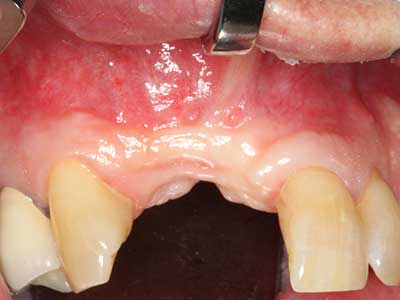

Abb. 2: Vertikaler und horizontaler seitlicher Oberkieferdefekt bei hoher Lachlinie mit Indikation zur präimplantologischen Rekonstruktion.

Abb. 21: Ausgedehnter OK-Frontzahndefekt mit Indikation zur Distraktionsosteogenese bei vernarbtem Weichgewebe nach Vor-Operation.